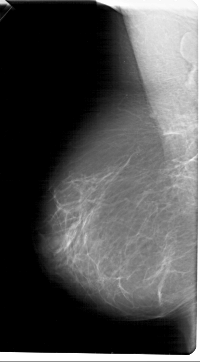

A_1452_1.LEFT_MLO

LEFT_MLO LINES 6871 PIXELS_PER_LINE 3796 BITS_PER_PIXEL 12 RESOLUTION 43.5 NON_OVERLAY